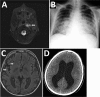

Description:Granulibacter bethesdensis is a pathogen reported to cause recurrent lymphadenitis exclusively in persons with chronic granulomatous disease. We report a case of fatal meningitis caused by a highly virulent G. bethesdensis strain in an adolescent in Europe who had chronic granulomatous disease.